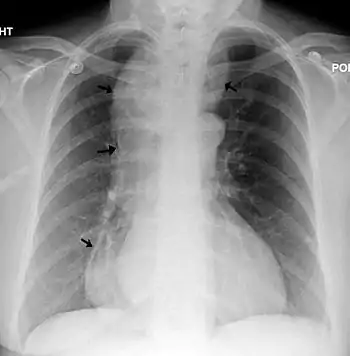

Aspecto radiográfico

Un esofagograma con rayos X (fluoroscopia), puede mostrar la disminución de los movimientos perstalticos, la dilatación del esófago medio y superior (proximal) y el estrechamiento del esófago en su parte inferior (distal), con estrechamiento en el esfínter esofágico inferior y reducción del diámetro en la unión gastro-esofágica. La imagen que proyecta se denomina clásicamente «en pico de loro» o «en cola de ratón». Por encima de la reducción, el esófago a menudo se observa con una dilatación de diversos grados a medida que poco a poco se va estirando en el tiempo. Por la falta de movimientos peristálticos, se suele observar en la radiografía un margen entre aire y líquido.